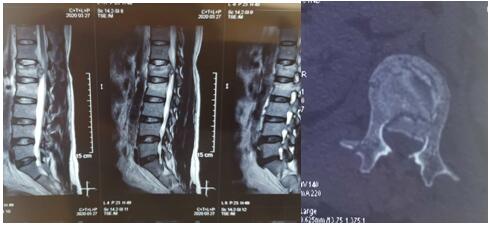

2020年3月26日夜,我院骨科二病区收住1例高处坠落伤致腰椎爆裂性骨折伴脊髓圆锥损伤、骨盆骨折、失血性休克合并右下肢深静脉血栓形成患者,曹某,男性,42岁。查体:腰段及骨盆处压痛,骨盆分离与挤压试验阳性,鞍区感觉减退。急诊行MRI示:腰1椎体爆裂性骨折、腰2椎体压缩性骨折,脊髓损伤;X线、CT+三维重建示:复杂骨盆骨折。患者系全身多处、多发复杂骨折,病情危重,手术风险及难度高。科主任王航辉博士组织科室骨干医生与神经介入科医生,经深入讨论后制定了详细、缜密、有序的综合救治方案,征得家属同意后,急诊在局麻下行下腔静脉滤网植入术,植入顺利,遂急诊在全麻下行腰1爆裂性骨折并脊髓圆锥损伤、腰2椎体压缩性骨折切开复位、椎板切开减压椎弓根螺钉内固定术,待病情稳定后再二期行骨盆骨折切开复位内固定术。

术前影像学资料如下: